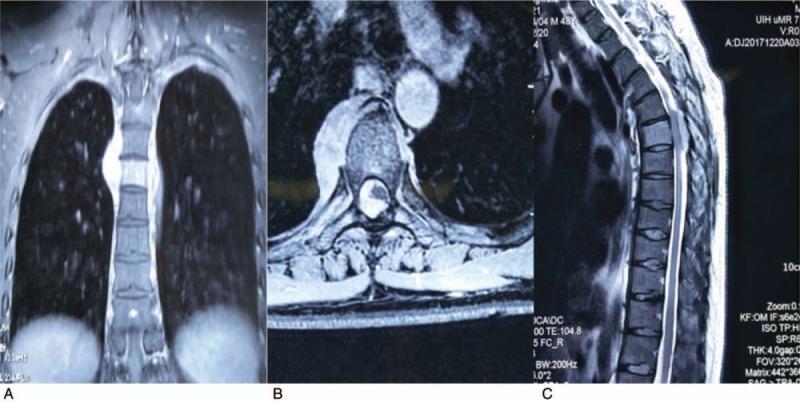

In immunophenotype analysis, CD2, CD3, CD7, and CD68 were positive and CD56 was suspiciously positive. Granzyme B and T-cell intracellular antigen (TIA-1) were also positive and in situ hybridization was positive for Epstein-Barr virus-encoded mRNA (EBER). Ki-67 was 60%+. Nuclide bone scan showed that the nuclide was unusually concentrated in the sixth thoracic vertebra which considered extremely active and slightly concentrated in the right sacrolilac joint. Magnetic resonance imaging detected an abnormal signal in the sixth thoracic vertebra with corresponding paravertebral and intraspinal occupying lesion. Based on the above features, a diagnosis of ENKTCL was made.

免疫表型分析中,CD2、CD3、CD7和CD68呈阳性,CD56可疑阳性。颗粒酶B和T细胞胞内抗原(TIA-1)也呈阳性,原位杂交检测到爱泼斯坦-巴尔病毒编码的mRNA(EBER)呈阳性。Ki-67为60%+。核素骨扫描显示核素异常浓聚于第六胸椎,提示该部位极度活跃,右侧骶髂关节有轻度浓聚。磁共振成像检测到第六胸椎有异常信号,伴有相应的椎旁及椎管内占位性病变。基于上述特征,诊断为ENKTCL。